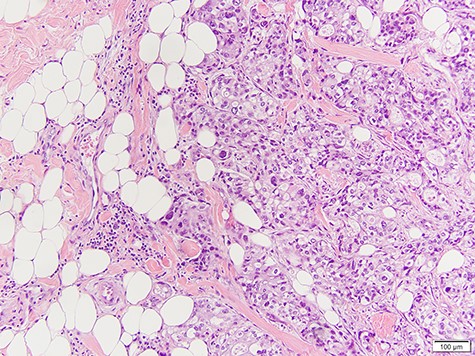

Physical examination yielded a 2-cm well-circumscribed, mobile, non-fixed, palpable mass in the upper outer quadrant of the left breast. She had no axillary lymphadenopathy, nipple retraction, excoriation, drainage or radiation-induced skin changes. Mammography and ultrasound of the breast mass demonstrated a 1.3 × 1.2 × 1.3-cm echogenic mass with irregular margins and posterior enhancement (Fig. 1). Core needle biopsy demonstrated adenocarcinoma that was morphologically identical to the patient’s known parotid malignancy.

She underwent surgical excision of the breast mass. Final pathology confirmed poorly differentiated carcinoma morphologically identical to her known parotid adenocarcinoma (Fig. 2).

Infiltration of high-grade poorly differentiated malignant cells from breast biopsy.